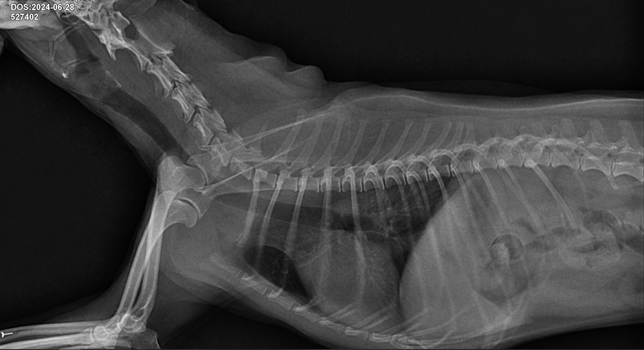

- 반려동물 건강반려동물Q. 강아지 허리 디스크 ct 사진 첨부합니다.. 재질문합니다..한달에 한번 주기로 깨갱 거리면서 특히나 혼자 붕가붕가하고 나서 그러는데요허리 디스크가 어느정도 상태인지 그리고 붕가붕가를 평생 못하게해야하는건지.. 알려주시면 감사하겠습니다....T4-6 vertebrae의 Rt. caudal articular process의 defect 확인됩니다. (→)• T13-L1 vertebrae의 IVDS(intervertebral disc space)가 주변에 비해 좁게 확인됩니다.T13-L1 vertebrae의 IVDS가 주변에 비해 좁게 확인되어 IVDD 가능성고려됩니다.

- 반려동물 건강반려동물Q. 선생님 저희 강아지 허리디스크가 어느정도인가요?한달에 한번 주기로 깨갱 거리면서 특히나 혼자 붕가붕가하고 나서 그러는데요 허리 디스크가 어느정도 상태인지 그리고 붕가붕가를 평생 못하게해야하는건지.. 알려주시면 감사하겠습니다....